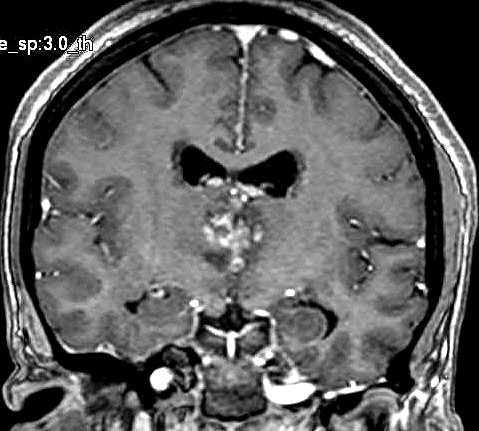

| Fem. 17a. |

| Nódulo sólido homogêneo preenchendo o III ventrículo, com limites precisos, com hipossinal em T1 e hipersinal em T2 e FLAIR, que se impregna por contraste paramagnético. Lesão menor implantada no assoalho do IV ventrículo provavelmente representa disseminação por via liquórica. |

| F. 17a. Tumor teratóide rabdóide atípico de III ventrículo. RM | HE | VIM, GFAP | HHF35, desmina, 1A4 | AE1AE3, EMA |